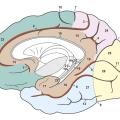

Anatomie de la mémoire

Il pourrait apparaître désuet de s’intéresser à l’anatomie macroscopique de la mémoire. Les mécanismes intimes de cette fonction cérébrale complexe mettent en effet en jeu des circuits neuronaux et des phénomènes de neurogenèse qui relèvent de mécanismes survenant à l’échelle microscopique.Néanmoins, certaines structures anatomiques…

1 - Les phénomènes mnésiques mettent en jeu à l’échelle microscopique des circuits neuronaux et des processus de neurogenèse. Néanmoins, certaines structures anatomiques clés comme l’hippocampe ou le lobe limbique ont un rôle central. L’hippocampe intervient dans l’acquisition, le stockage et la distribution des informations…